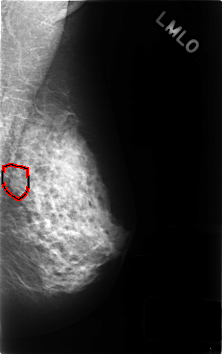

ics_version 1.0 filename C-0440-1 DATE_OF_STUDY 21 7 1995 PATIENT_AGE 48 FILM FILM_TYPE REGULAR DENSITY 3 DATE_DIGITIZED 23 11 1998 DIGITIZER LUMISYS LASER SEQUENCE LEFT_CC LINES 4584 PIXELS_PER_LINE 2912 BITS_PER_PIXEL 12 RESOLUTION 50 NON_OVERLAY LEFT_MLO LINES 4592 PIXELS_PER_LINE 2880 BITS_PER_PIXEL 12 RESOLUTION 50 OVERLAY RIGHT_CC LINES 4552 PIXELS_PER_LINE 2920 BITS_PER_PIXEL 12 RESOLUTION 50 NON_OVERLAY RIGHT_MLO LINES 4584 PIXELS_PER_LINE 2888 BITS_PER_PIXEL 12 RESOLUTION 50 NON_OVERLAY |

FILE: C_0440_1.LEFT_MLO.OVERLAY TOTAL_ABNORMALITIES 1 ABNORMALITY 1 LESION_TYPE MASS SHAPE ROUND MARGINS MICROLOBULATED ASSESSMENT 3 SUBTLETY 3 PATHOLOGY BENIGN_WITHOUT_CALLBACK TOTAL_OUTLINES 1 BOUNDARY |